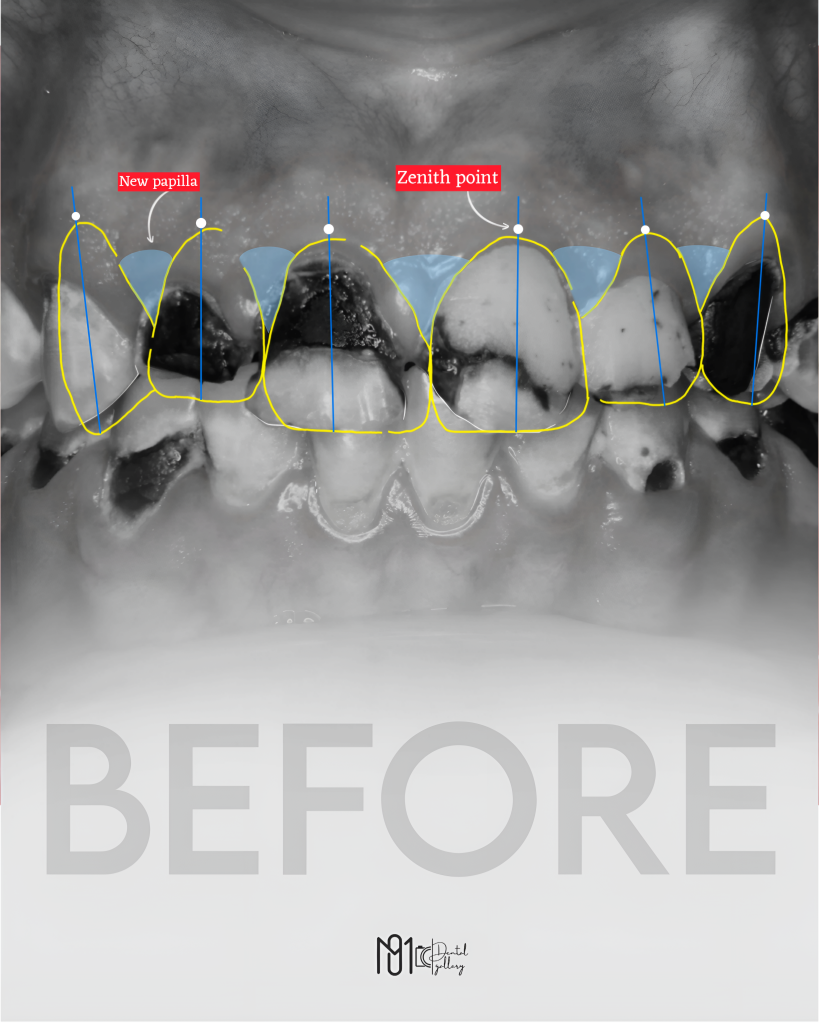

The case involved managing extensive carious lesions across both arches, performing root canal treatments, direct and indirect restorations, and even a periodontal surgical procedure.

I treated multiple deep caries cases using Immediate Dentin Sealing (IDS), performed Composite Resin Restorations (CRR) for both anterior and posterior teeth, and placed temporary restorations to maintain occlusion before the final prostheses.

This case involved almost every aspect of dentistry — diagnosis, endodontics, restorative, prosthodontics, and periodontal surgery — and I couldn’t be prouder of how far I’ve come through it.